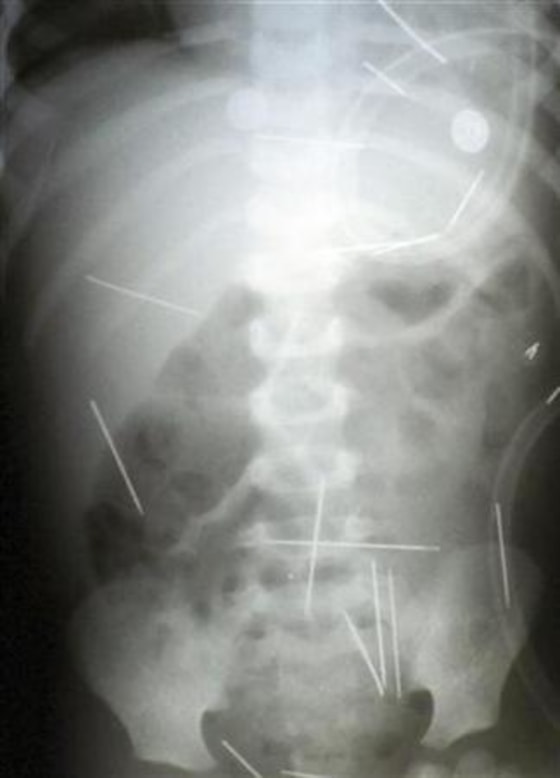

But the pain led the toddler to complain to his mother, and on Dec. 10 she took him to a hospital where X-rays revealed about 30 needles lodged throughout his body.

The boy underwent a five-hour operation in the northeastern city of Salvador on Friday to remove four rusty needles that most threatened his life, near his heart and in his lungs.

Doctors said Sunday the child is doing well and will likely undergo two more surgeries, the next one on Wednesday at the earliest, to extract needles up to 2 inches long from his abdomen and spine.